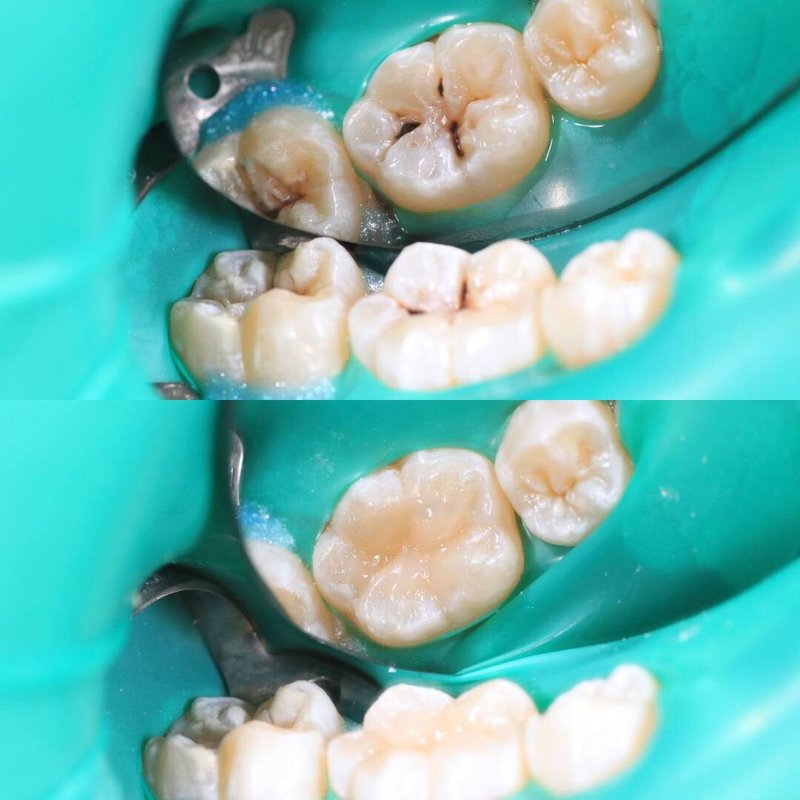

Фотогалерея